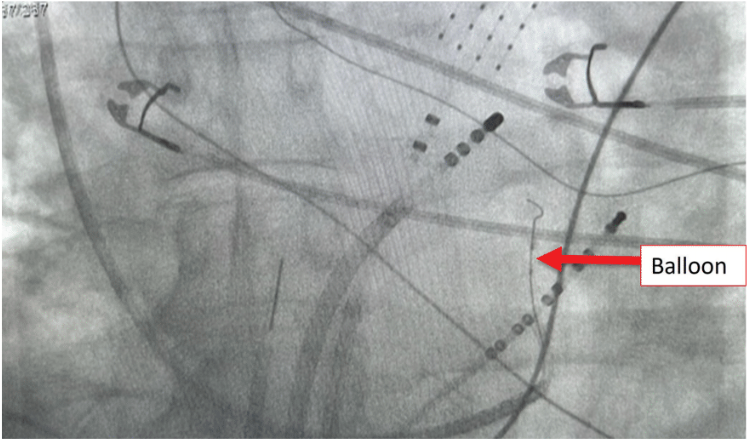

Following the initial approach of endocardial mitral ablation, alcohol VOM ablation was then performed (Figure 2). Remarkably, AFL terminated during the first injection of alcohol, indicating the effectiveness of the procedure in real time (Figure 3). A total of 10 cc of alcohol was injected into the VOM. Subsequently, a mitral isthmus conduction time of 151 msec was achieved, suggesting complete block.

Alcohol VOM ablation was then performed. Video 2 demonstrates the VOM during contrast injection through the LIMA guide catheter. After occluding the VOM with a 2.0 x 6 balloon, 10 cc of 99% alcohol was injected.